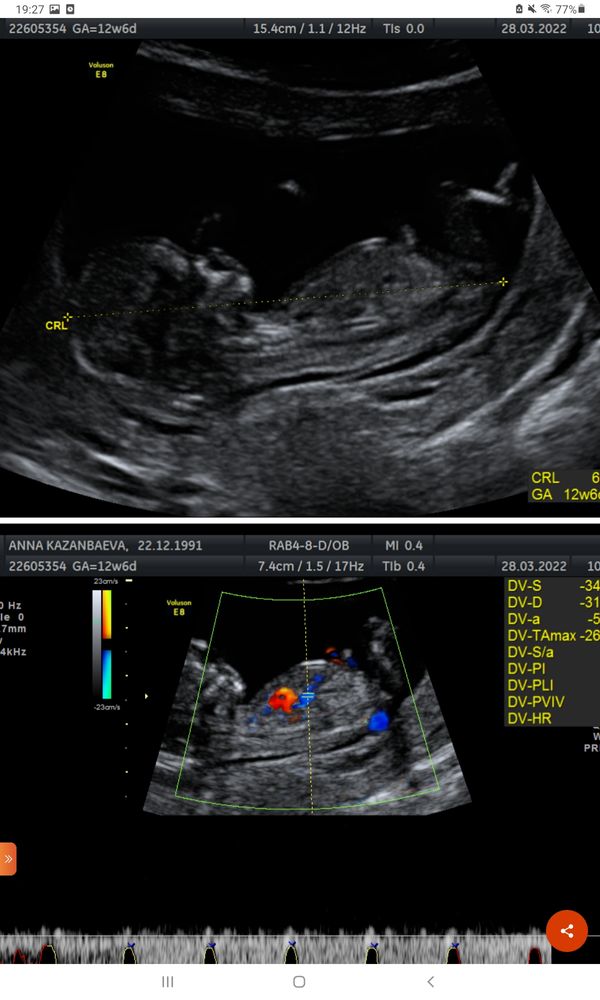

Мальчик или девочка?🙏❤🙂

Изображение На мальчика похоже. Сейчас покажу как у меня, сказали девочка...

Узнать пол по крови Половой бугорок